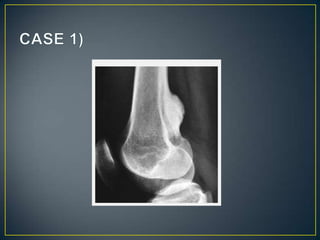

• The site of a bone lesion is an important feature, because

some tumors have a predilection for specific bones or

specific sites in the bone .The sites of some lesions are

so characteristic that a diagnosis can be suggested on

this basis alone, as in the case of parosteal

osteosarcoma or chondroblastoma . Moreover, certain

entities can be readily excluded from the differential

diagnosis on the basis of the lesion's location